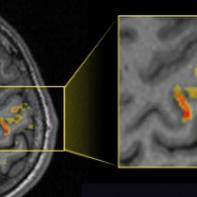

The study of human MRI and of functional MRI is a prime example of contemporary multidisciplinary science; where Physics, Chemistry, Biology and Engineering meet. In our lab we integrate these fields aiming to develop new imaging methods and new tools for functional brain measurements. The study relies on the one hand on a physics background, for the development of new MRI techniques, on the other hand on a neurobiology background, to perform the actual human volunteer studies. Our lab’s research focuses on ultra-high field MRI, which allows to achieve sub-millimeter resolution. We explore methods to study neurofeedback processes and underlying neurovascular responses.

Developing new tools for human MRI, especially at ultra-high field 7T MRI scanner, aiming to better understand the human brain function